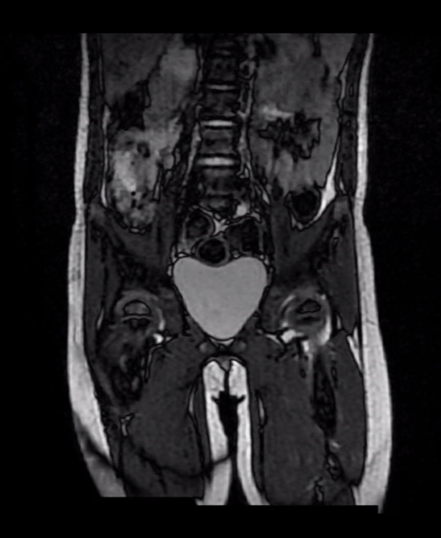

기본적으로 시행하는 x-ray 및 피검사 외에도 MRI 검사를 통해서 고관절 내 농양 형성 여부 및 골수내 침범을 확인하게 됩니다.

- 먼저, 발열/증상의 정도/피검사 수치를 바탕으로 감염성 고관절인지를 의심한다.

- 조금이라도 감염성 고관절의 가능성이 있다면 MRI 검사와 응급수술을 시행한다.